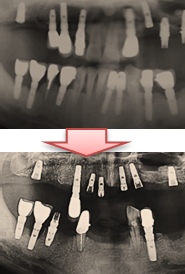

모든 임플란트를 제거한 후 다시 임플란트를 하는 과정은 그리 만만치가 않다.

뼈 이식한 후 단계적으로 진행해야 하기 때문이다.

모든 치아를 임플란트로 하는데 보통 1년 반이라는 시간이 걸린다.